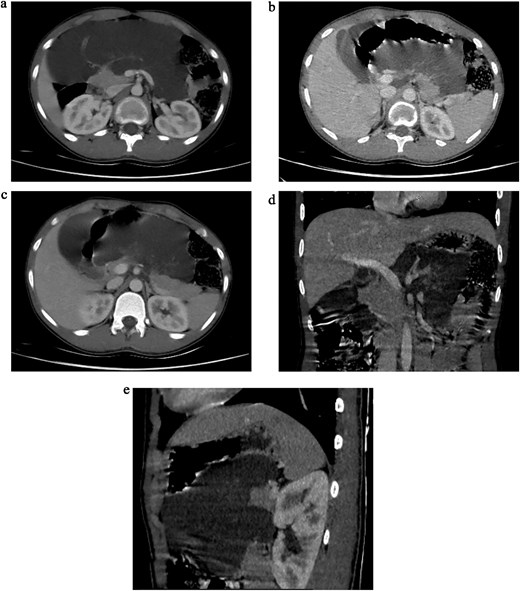

Initial ultrasonography (USS) revealed multiple cystic lesions with parenchymal distortion in the tail of the pancreas. A contrast-enhanced computed tomography (CT) scan showed a large, lobulated, nonenhancing hypodense lesion (6.6 × 16 × 16 cm) with internal septations involving the neck and body of the pancreas. The lesion extended superiorly to the liver hilum and greater curvature of the stomach, anterolaterally to the anterior abdominal wall, and inferiorly to the umbilicus level (L4 vertebra), with no evidence of invasion (Fig. 1a–e). Differential diagnoses included cystic neoplasm and lymphangioma.

(a) Axial sections of CT abdomen (arterial phase) showing cystic mass in relation to pancreas. (b) Axial sections of CT abdomen (arterial phase) showing cystic mass in relation to pancreas. (c) Axial sections of CT abdomen (venous phase) showing cystic mass in relation to pancreas. (d) Coronal section of CT abdomen (venous phase) showing cystic mass in relation to body and tail of the pancreas. (e) Sagittal section of CT abdomen (venous phase) showing cystic mass in relation to body and tail of the pancreas.